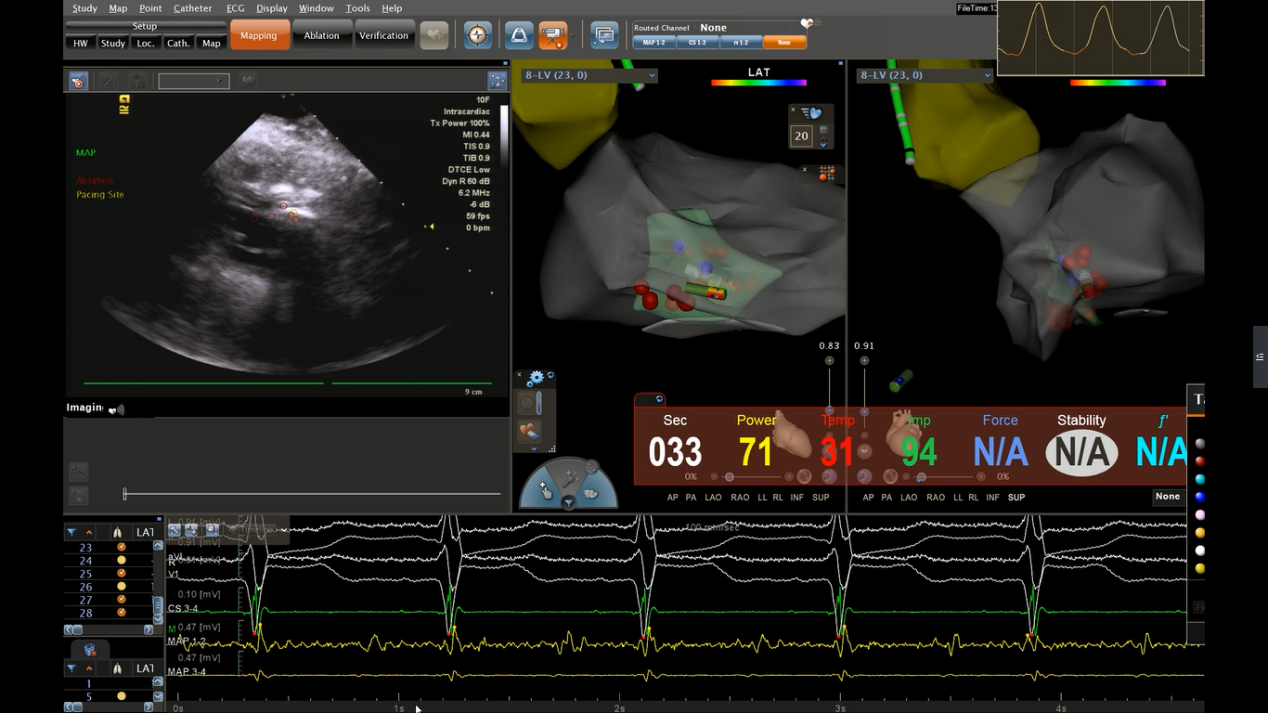

心腔内超声导管指导下的三维射频消融术可实时获得心腔内解剖结构、精确指导消融导管到达靶点部位,心腔内超声还能实时监测术中腔内变化,第一时间发现心房内微血栓形成和心包积液等并发症,并实现介入手术的“零射线”,真正意义上实现了绿色电生理,极大地提高了电生理手术的成功率及安全性。随着该项技术在我院的成功应用及普及,将治愈我省更多的复杂性心律失常患者。

ICE实时监控下行室间隔射频消融